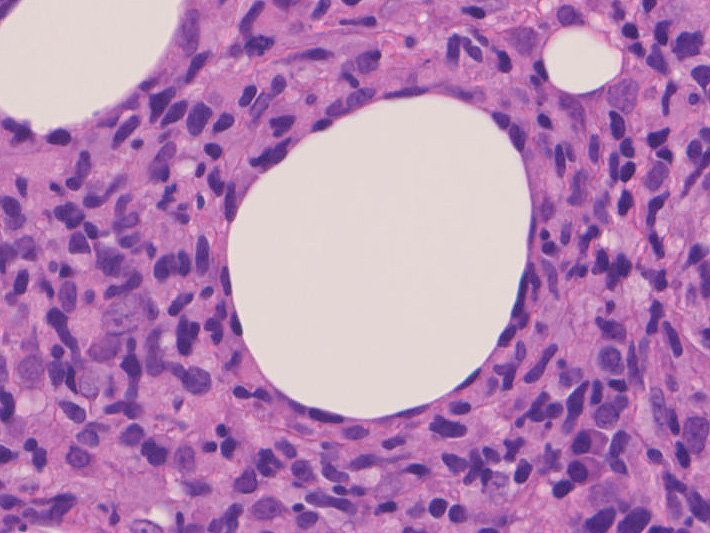

リンパ腫の定義: SPTCLは成熟細胞障害性T細胞(cytotoxic T-cell)由来で、皮下組織に脂肪識炎に似た組織像を呈しながら増殖する悪性リンパ腫。

組織所見*16*17*18

皮下組織に優位な, 小~中型 Tリンパ球の密な浸潤が特徴。ときに大型リンパ球や組織球が混在する。 リンパ球の異型は, わずかなものから明瞭な異型を示す症例までさまざまである。